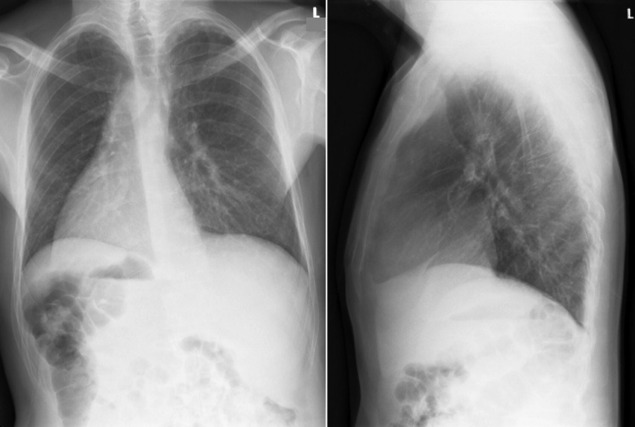

Situs refers to the position/arrangement of the thoracic and abdominal organs ( Figs 20-1 to 20-5 ). The posteroanterior/frontal chest radiograph is able to depict the location of the heart, the left ventricular apex, the aorta, and the gastric air bubble, and it may thereby determine situs.

Situs inversus: right apex and right-sided stomach ( Fig. 20-7 )